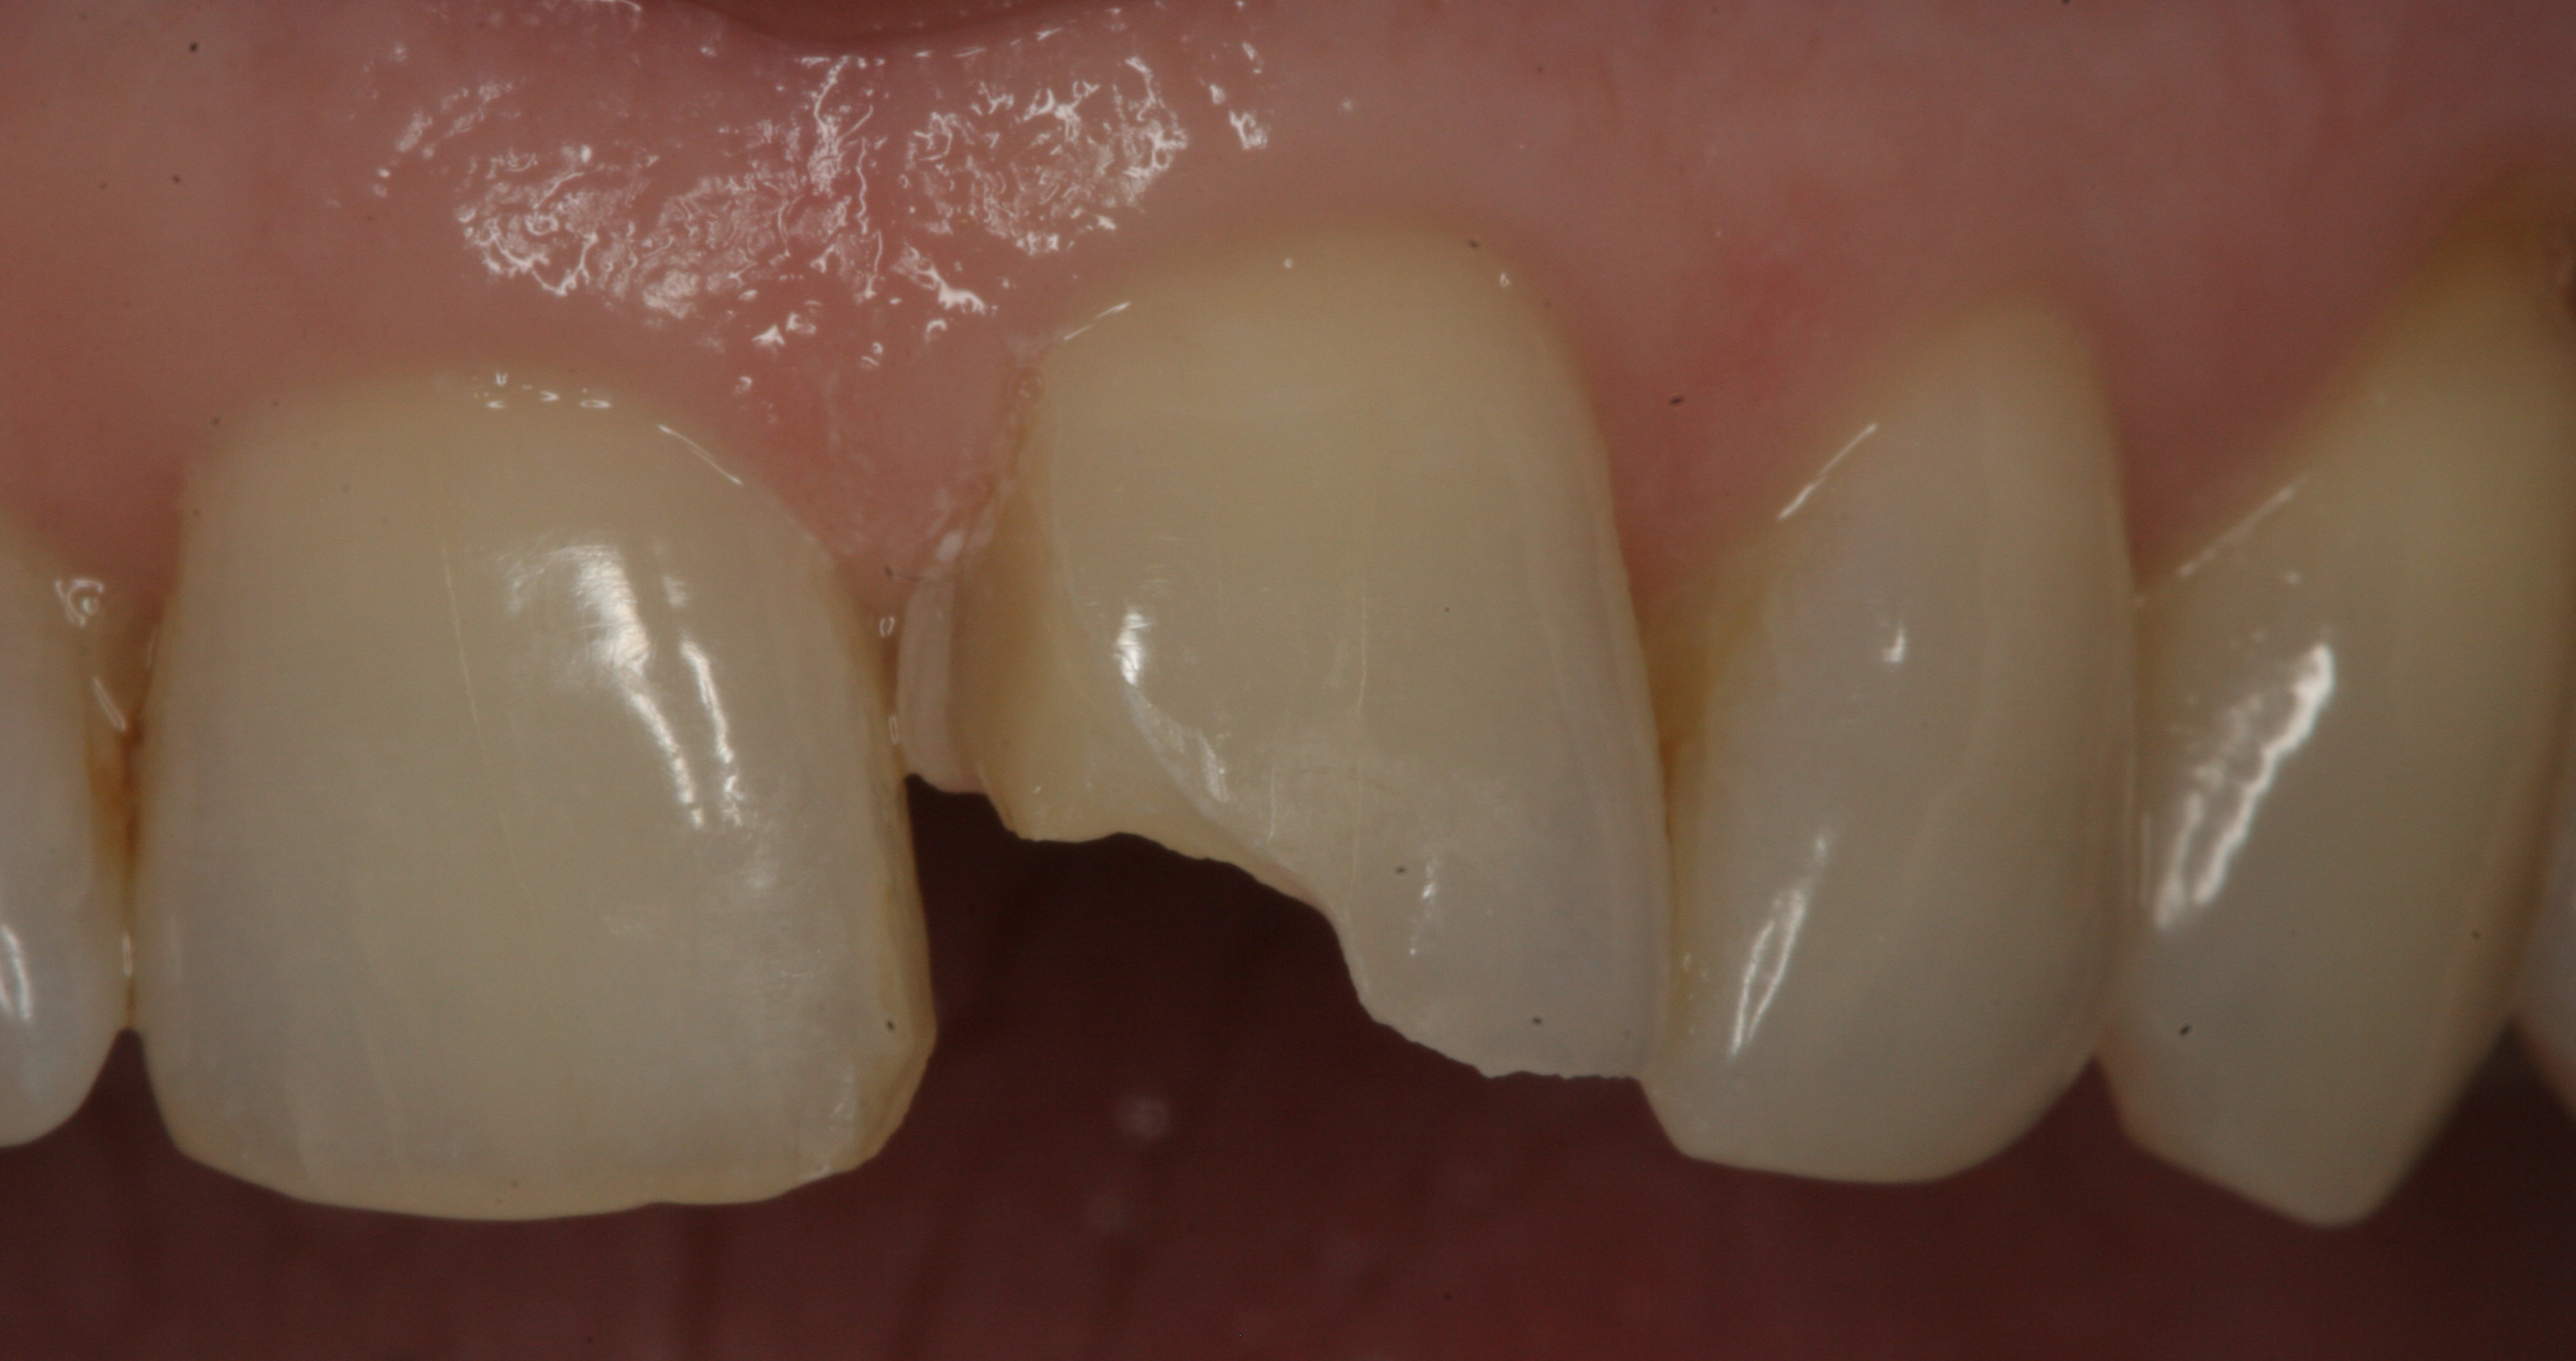

Fig 5. Postoperative view of the restored tooth using a smart-matching resin composite without using a mirror-backing technique. Note the lower value of the incisal edge.

Figure 5

In restorative cases where a large portion of the incisal edge is missing or when extending the length of an anterior tooth is required, it is suggested that a lingual wall or "mirror-backing" be created to manage the translucency projecting the darkness from the back of the mouth (Figure 4 and Figure 5).40 The technique involves building a wall on the lingual aspect of the restoration with the opaque shade. This creates a less translucent lingual aspect that blocks the darkness from the back of the mouth and thus prevents it from showing through. After this wall is constructed, the more translucent smart-matching material can be applied to the front of the wall.